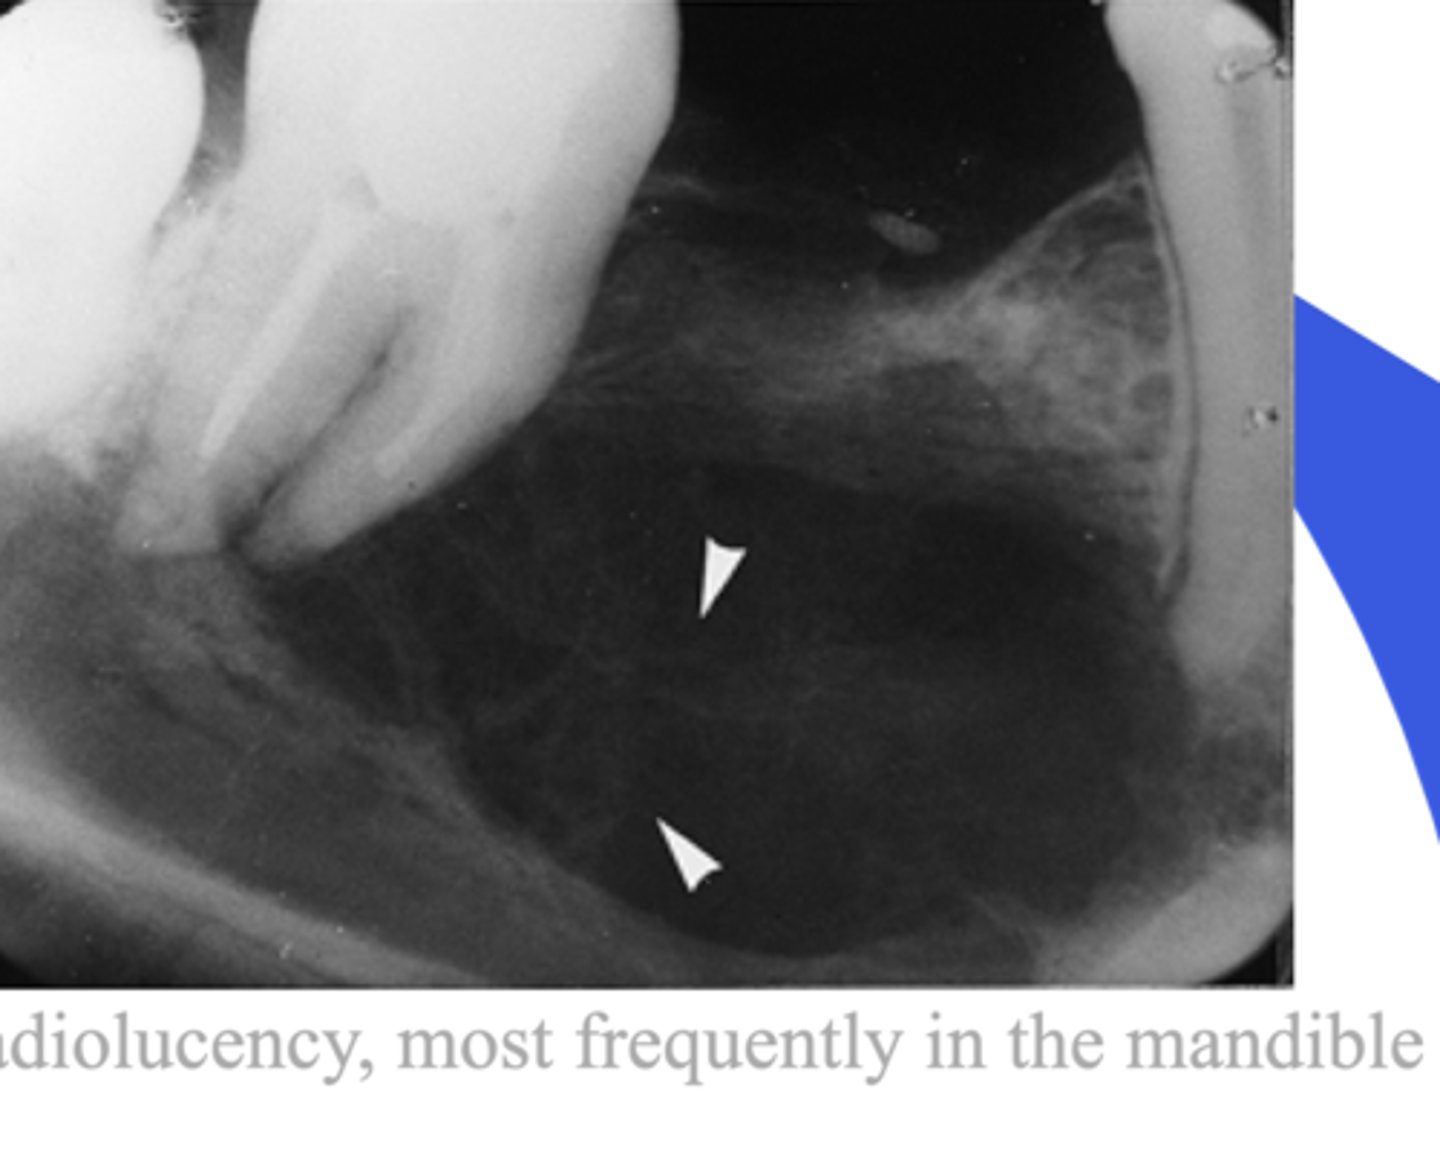

Central giant cell granuloma

- RL --> will keep growing if left alone

- Always check tooth vitality

- Beehive combe (multilocular)

- more common in younger pts